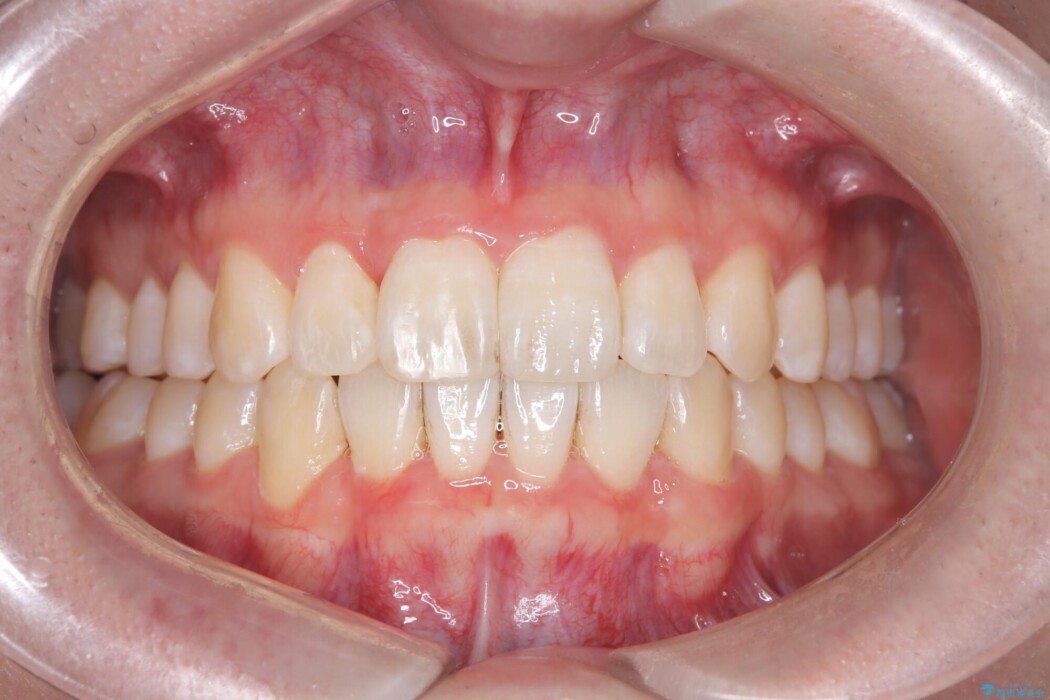

患者様の意識も高くしっかりと装着していただけたため、計画通りのきれいな歯列弓となりました。仕上がりにとてもご満足いただけました。

もし他院で抜歯矯正の判断がされても状態によっては非抜歯での矯正治療が可能な場合もありますので、ぜひ一度ご相談ください。